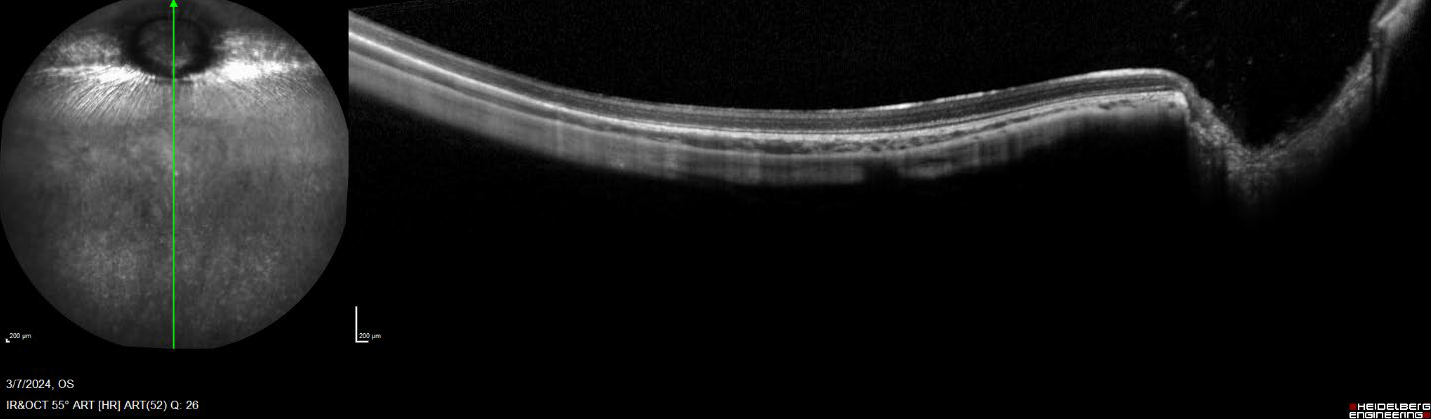

• Optical coherence tomography is an ocular imaging modality that employs a laser beam at varying wavelengths to provide cross-sectional images of ocular tissues. This non-invasive technique offers the opportunity to collect and analyze the longitudinal safety and efficacy data that is required to understand ocular disease pathology and the effectiveness of potential treatments. With the state-of-the-art Heidelberg Spectralis HRA+OCT system, the scientists at GD3 can provide personalized, high-resolution scanning and analysis strategies to meet your needs.

Figure 2. Vertical, single line, wide field OCT scan of a rabbit retina

Figure 3. Horizontal, single line, OCT scan of a mouse retina with 30ยบ lens.